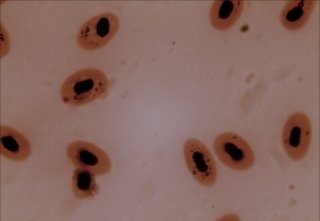

적혈구는 핵이 없는 오목한 원반 모양이다. 이러한 모양은 표면적을 넓혀 산소 교환 효율을 높이고, 좁은 모세혈관을 통과하기 쉽게 한다. 전자현미경으로 관찰하면 한국인의 적혈구는 평균 직경 7µm~8µm, 두께 2.2µm 정도이며, 중심부는 0.46µm~1.16µm 정도로 더 얇다.[76]

포유류의 적혈구는 성숙 과정에서 핵을 잃어 헤모글로빈을 위한 공간을 확보한다. 포유류의 적혈구는 전형적으로 양쪽이 오목한 원반 모양이며, 단면은 아령 모양이고, 원반 가장자리는 환형체 모양이다. 이러한 모양은 가스의 확산을 용이하게 하기 위해 높은 표면적 대 부피(SA/V) 비율을 허용한다.[16]